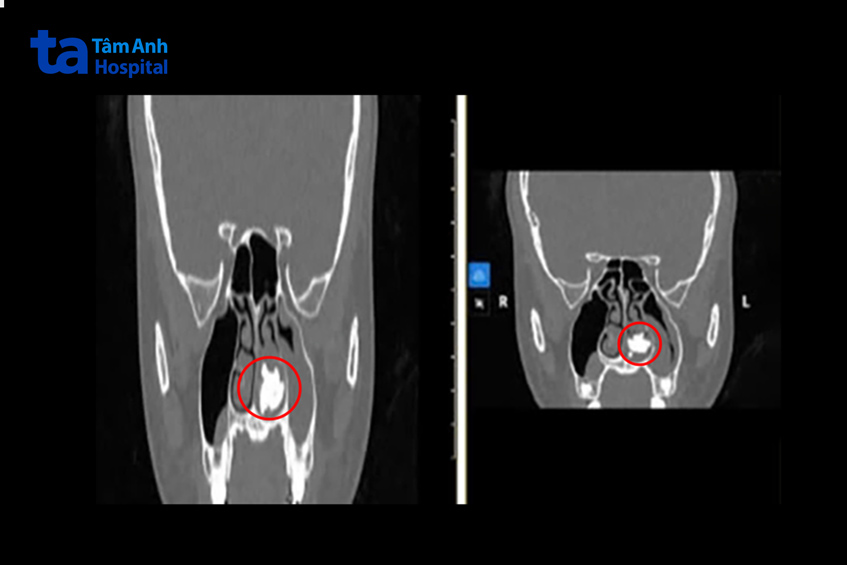

Nghi ngờ sỏi mũi, bác sĩ Duy chỉ định người bệnh chụp CT hàm mặt để đánh giá tình trạng.

Kết quả cho thấy người bệnh bị sỏi mũi hiếm gặp ở vùng mũi xoang, kích thước sỏi mũi to khoảng 3×2 cm, bít tắc gần toàn phần khe mũi trái. Sau đó người bệnh được tiến hành lấy sỏi mũi tại phòng mổ dưới gây mê. Thời gian thực hiện khoảng 30 phút. “Kích thước sỏi mũi to khoảng gấp bốn lần kích thước răng trong cùng hàm dưới của người bệnh”, bác sĩ Duy nói. Tái khám sau 2 tuần, chị H. hết các triệu chứng nghẹt mũi, chảy mũi hôi, đau vùng mũi.